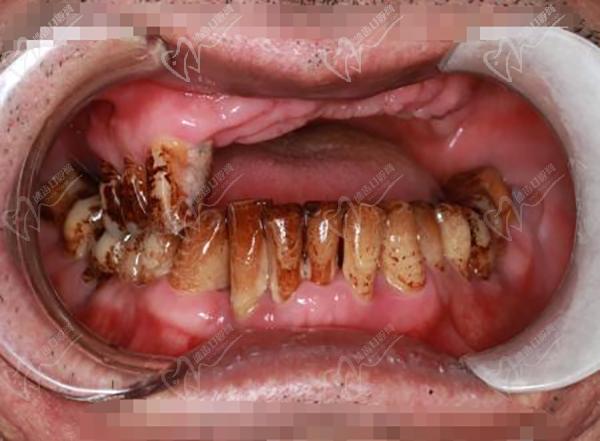

作為廣州市實力強勁的綜合性口腔醫(yī)院,暨南大學穗華口腔在種植牙領(lǐng)域名聲在外。醫(yī)院擁有一批經(jīng)驗豐 富的種植醫(yī)生,例如馮智強醫(yī)生,并擅長各種種植牙手術(shù),包括單顆種植、多顆種植、微創(chuàng)種植、數(shù)字化種植、半口/全口種植,甚至難度技術(shù)高的穿顴穿翼種植。

半口種植牙·集采種牙:21860元起

全口種植牙·集采:42720元起